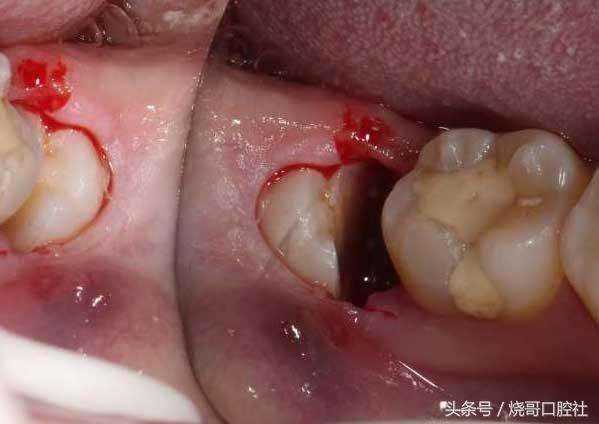

关于缝不缝线具体得看创口大小,术后较大创口都需要缝线,这样才能止血预防感染,而创口小的直接不用处理,靠血凝块自主保护,所以千万不要去破坏它,也不能吐口水。

创口不拆线危害将会升级!

1、食物残渣会更容易聚集在缝合线上,细菌在线周围组织滋生,感染牙龈后炎症是一回事,关键牙槽骨逐渐吸收,这才是最可怕的,因为牙龈也会跟着萎缩。